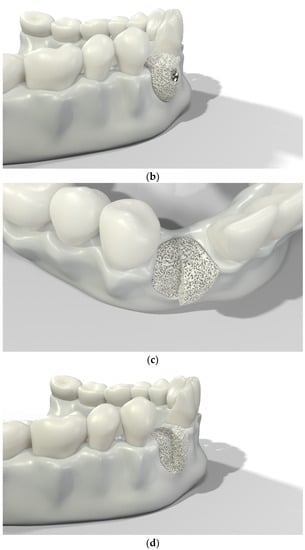

Over-contouring was defined as an over-augmentation of the alveolar process beyond the extent of the adjacent bone level (Figure 1). The reason for over-augmenting the alveolar process is often an anticipated shrinkage of the bone substitution material during the healing phase. Two patients were selected as examples to illustrate the term “over-contouring”. Patient 1 showed a Class III defect in the maxilla, and the alveolar ridge augmentation performed for correction was over-contoured (Figure 2). Patient 2 also showed a Class III defect in the maxilla, but the alveolar ridge augmentation performed for correction remained at the level of the surrounding bone (Figure 3).

Figure 1.

Graphical 3D models to demonstrate surgical over-contouring during augmentation of the alveolar process. (a) Lateral view of the mandible with a single-tooth gap on the position of the second right incisor; the bone defect was compensated without exceeding the extent of the adjacent bone level. (b) Lateral view of the mandible with a single-tooth gap on the position of the second right incisor; the bone defect was over-compensated by an over-augmentation of the alveolar process beyond the extent of the adjacent bone level. This is defined here as “over-contouring”. (c) Isometric view of the mandible with a single-tooth gap on the position of the second right incisor; the difference between appropriate augmentation (left half) and over-contouring (right half) is clearly visible. (d) Lateral view of the mandible with a single-tooth gap on the position of the second right incisor; the difference between appropriate augmentation (left half) and over-contouring (right half) is easily recognizable.